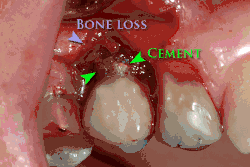

Ebenso kann eine fehlerhafte Suprakonstruktion die Periimplantitis begünstigen. Hierzu zählen eine mangelhafte Hygienefähigkeit des Implantats, Spannungen durch prothetische Fehlpassung oder Mikrobewegungen der Suprastruktur. Auch die Nichtentfernung von subgingivalen Überschüssen des Befestigungszements, mit dem die Suprakonstruktion (Zahnkrone) auf dem Implantat befestigt wird, bildet einen Entzündungsreiz, der zu einer Periimplantitis mit Knochenabbau führt.[5]